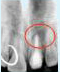

Tooth with Fracture Extending Sub-Gingivally

X-ray showing

picture line